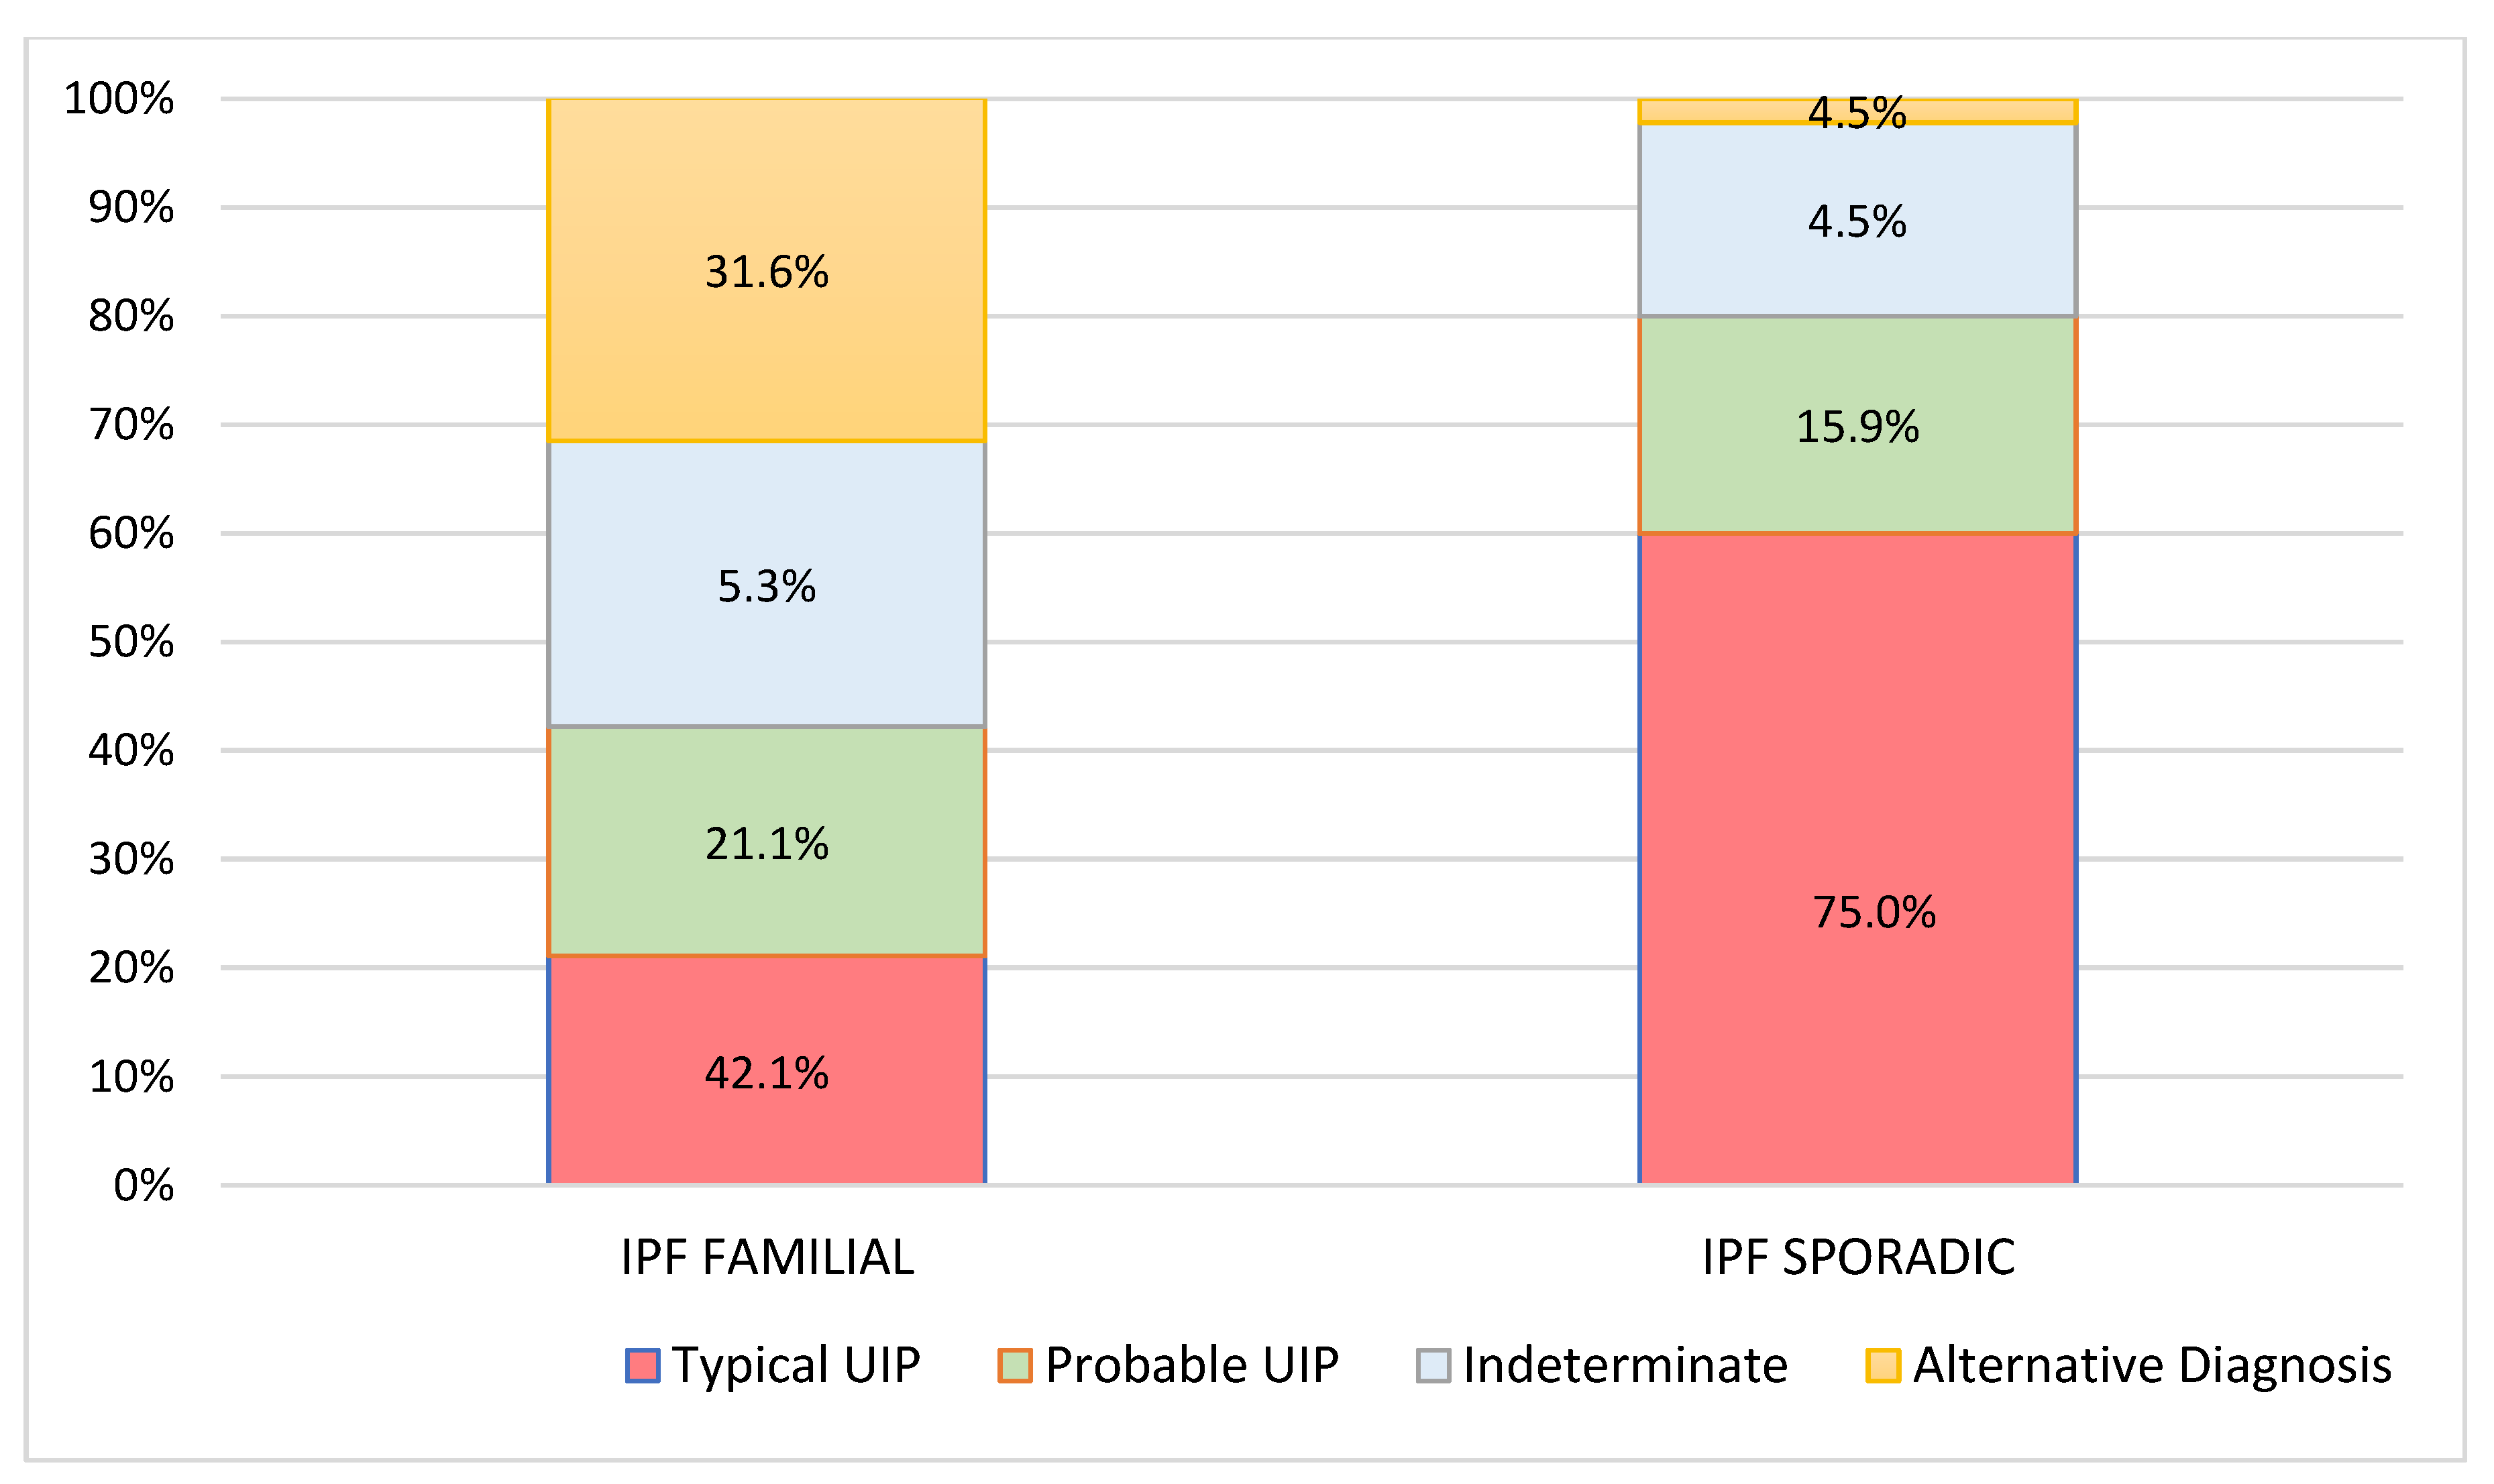

| Pattern at Diagnosis (N, %) | |||

| typical UIP | 4 (21.1%) | 27 (60.0%) | |

| probable UIP | 4 (21.1%) | 9 (20.0%) | 0.001 |

| Indeterminate | 5 (26.3%) | 8 (17.8%) | |

| Alternative Diagnosis | 6 (31.6%) | 1 (2.2%) | |

| Pattern at 2 years (N, %) | |||

| Typical UIP | 8 (42.1%) | 33 (75.0%) | 0.014 |

| Probable UIP | 4 (21.1%) | 7 (15.9%) | |

| Indeterminate | 1 (5.3%) | 2 (4.5%) | |

| Alternative Diagnosis | 6 (31.6%) | 2 (4.5%) | |